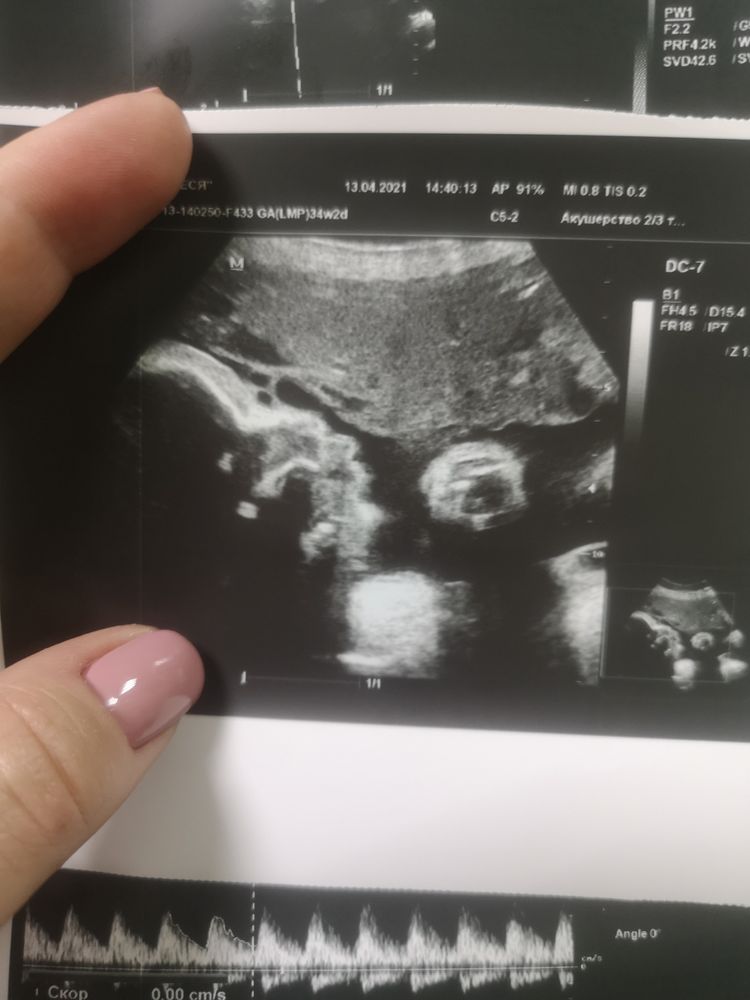

Срок 36 неделя... Переживаю. Каждую ночь рыщу в интернете по показателям узи. Все время кажется, что с сыночком что-то не так. Все из-за того, что на первом скриниге, кровь не много не вошла в какие-то там параметры. На втором все было хорошо. А на третьем, поставили звур, правда через 10 дней другой узист отставания не увидел. Теперь я смотрю на снимок лица, и мне кажется, что что-то не так с носом. Ужасно переживаю. С первой дочерью таких загонов не было. Забеременела когда хотела. А этого малыша мы три года ждали....

У меня вот тоже по крови не очень результаты, сдавала два раза. Тоже переживаю, но стараюсь не раскисать. Зачем малышку тревожить. Всё У вас хорошо. На снимке не понимаю, что вам не нравится. Это же не фотография, а снимок УЗИ. Он не всегда идеальный получается. Цифры же наверное в норме?